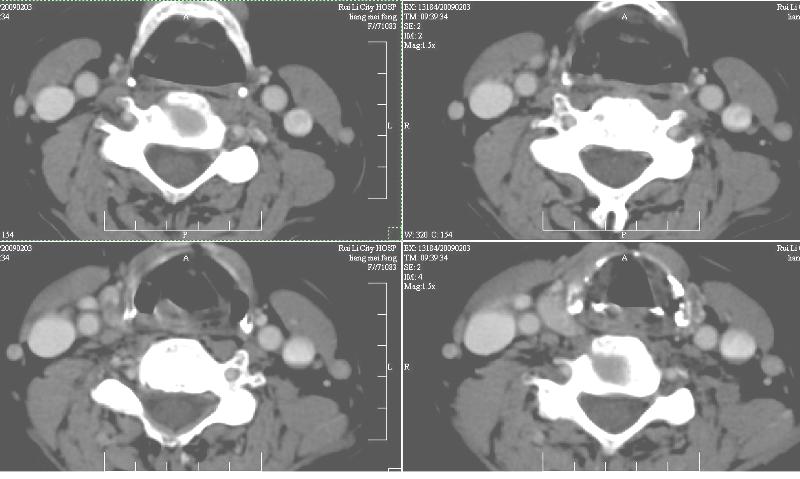

增强:1、双侧甲状腺肿。2、平扫甲状腺内多发占位病变,增强显示不清楚,境界欠清,请结合临床考虑甲状腺瘤。

右侧甲状腺占位及右侧淋巴结肿大,考虑甲状腺癌!期待结果!

强化效果一般,未见明显恶性征象。

1)弥漫性甲状腺肿。2)甲状腺多发性腺瘤?